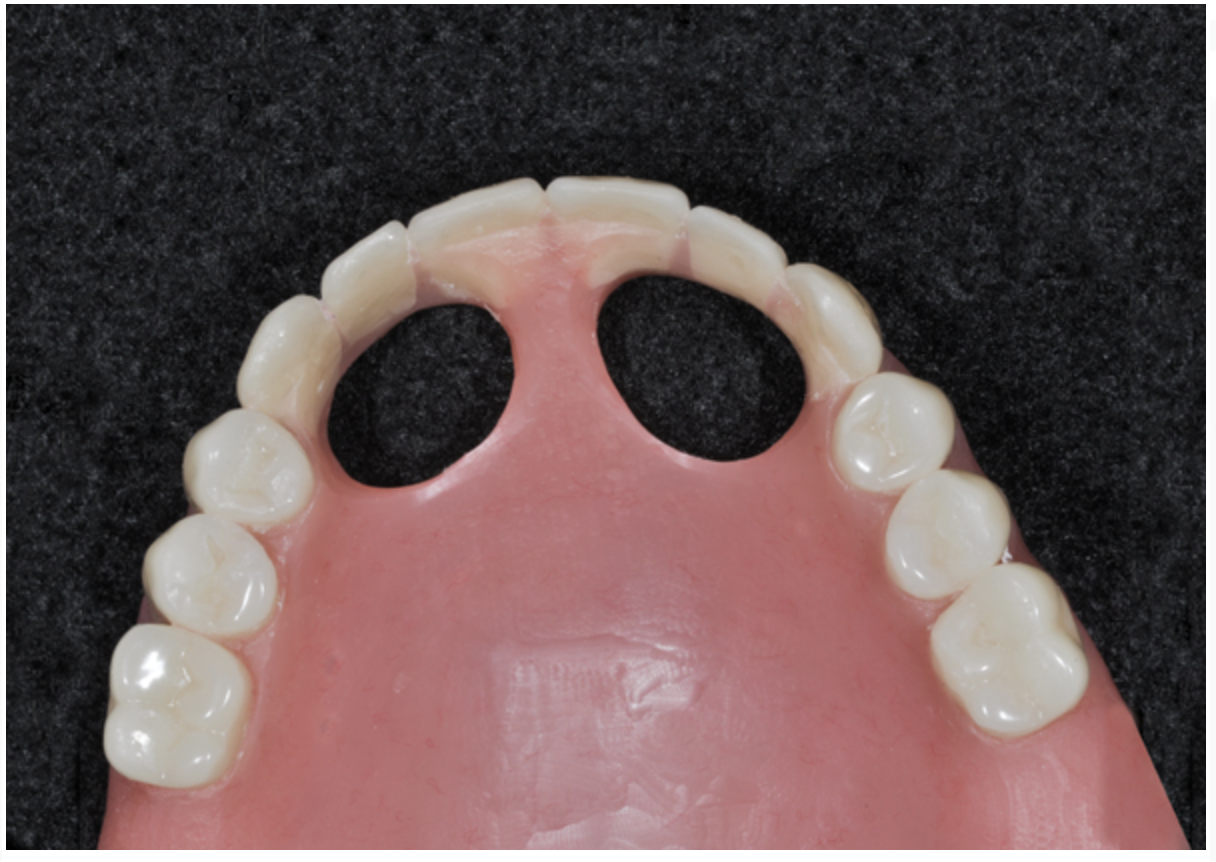

Fig 6. Completed diagnostic wax-up for maxillary and mandibular All-on-4 full-arch rehabilitation.

Figure 6